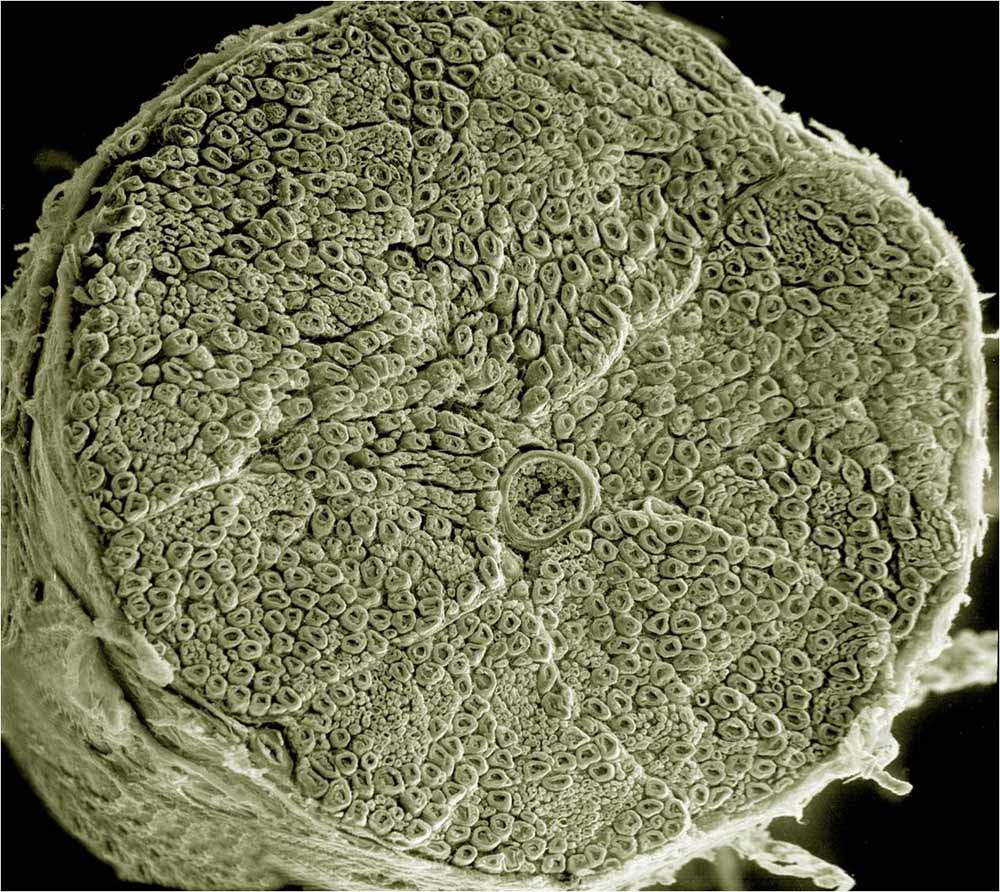

An electron microscopy image of a cross-section of a spinal nerve, illustrating the complexity on a tiny scale. This is why nerve repair needs to happen on the cellular level with stem cells, as it cannot be repaired in any other way.

Image from UCSD tumblr

Spinal trauma can disrupt ascending and descending axonal pathways that lead to inflammation, demyelination and loss of neural cells (neurons). Depending on the site of injury, functional disorders induced by cellular damage usually results in the inability to move, sensory loss and/or lack of autonomous nervous system control.